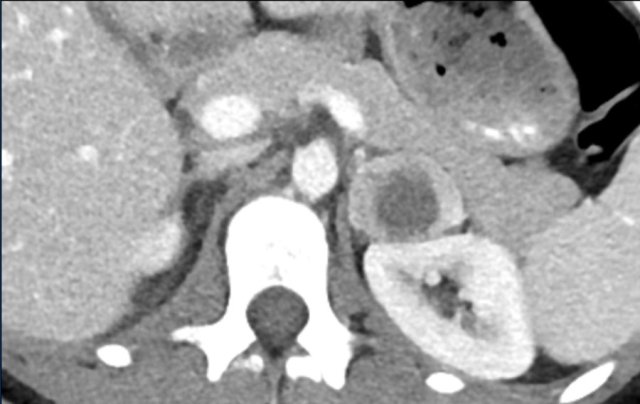

First postoperative axial venous phase CT performed 3 months after left adrenalectomy for a large adrenocortical carcinoma showing an enhancing nodule posterior to the left kidney.

Restaging FDG PET-CT showed intense uptake in only this lesion, which proved to be a metastasis on subsequent follow-up imaging.

The left renal subcapsular hematoma is unrelated.